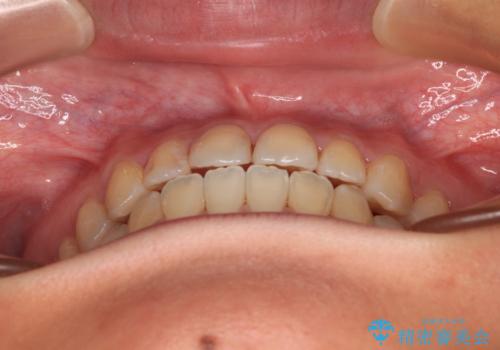

前歯のクロスバイトを治したい ワイヤー装置による矯正治療

- 前歯の反対咬合を気にして来院された患者様です。

マウスピース矯正も提案しましたが、しっかりと使用する自信がないとのことで、ワイヤー装置により矯正治療を行うこととしました。

クロスバイト改善まではスムーズに進みましたが、その後は強い舌の突出癖によりオープンバイトの期間が長く続きました。

舌のトレーニングをしっかりと実施してもらい、何とか仕上げることができました。